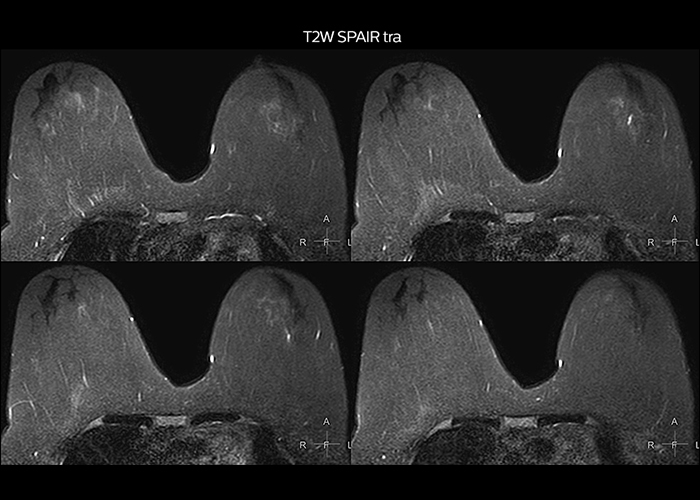

“Most important, Multiva satisfies our clinical imaging needs very well,” says Mr. Tuna. “Many features of Multiva have become similar to the Ingenia system. Even in more complex imaging such as abdominal and cardiac, the image quality and performance of Multiva is better than we expected. General surgeons and physicians from our hospital’s internal medicine department prefer to refer to us because of this.”

“To avoid coil changes we plan examinations of similar anatomies back to back, such as head and spine. Multiva helps us here a lot because coils don’t need to be changed frequently. Moreover, thanks to parallel imaging technology and 16-channel HeadSpineTorso and 8-channel MSK coils we are able to achieve excellent image quality. In this way Multiva helped us to increase both image quality and productivity.”